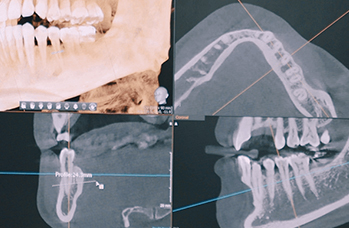

3D 디지털 진단을 통한 체계적인 계획

전체 임플란트는 위턱과 아래턱의 교합, 잇몸뼈의 상태 및

얼굴 변화 등 모든 것을 고려해 식립해야 합니다.

서울더자연치과는 3D 디지털 기술의 정밀 진단을 바탕으로

수술 계획을 세워 수술을 집도합니다.

잇몸뼈가 얇은 상태

잇몸뼈 충분히 이식 후 임플란트 식립

성공을 위한 노하우, 잇몸뼈 재건 기술

이 때, 치조골 이식을 병행하여 잇몸뼈 재건 후 안정적인 임플란트 식립을 하고 있습니다.

치료기간 : 2021.04.12~2021.09.15